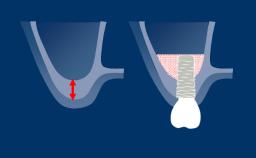

The use of dental implants has become a standard treatment in many clinical situations. However, in order to achieve optimal functional and esthetic results, the clinician has to assess the complexity and risks associated with an implant therapy before starting the treatment.

The SAC classification system differentiates between Straightforward, Advanced and Complex treatments. It was first proposed in a textbook on minor oral surgery for general dentists. In a Consensus Conference in 2007, the ITI reviewed and refined the SAC Classification for use in implant dentistry. The proceedings were published in a text book in 2009 and since then serve as an important tool in implant dentistry.